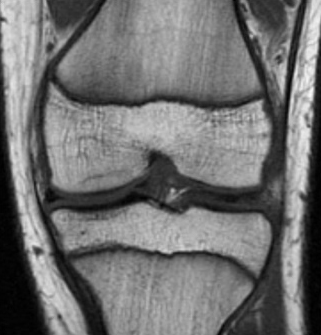

Coronal MRI image of the talus, showing an osteochondral lesion on the medial aspect of the talar dome

Gupta RK, Kansay R, Aggarwal V, et al. Osteochondritis dessicans of the talus in a 26-year-old woman. BMJ Case Reports 2009; doi:10.1136/bcr.06.2008.0091